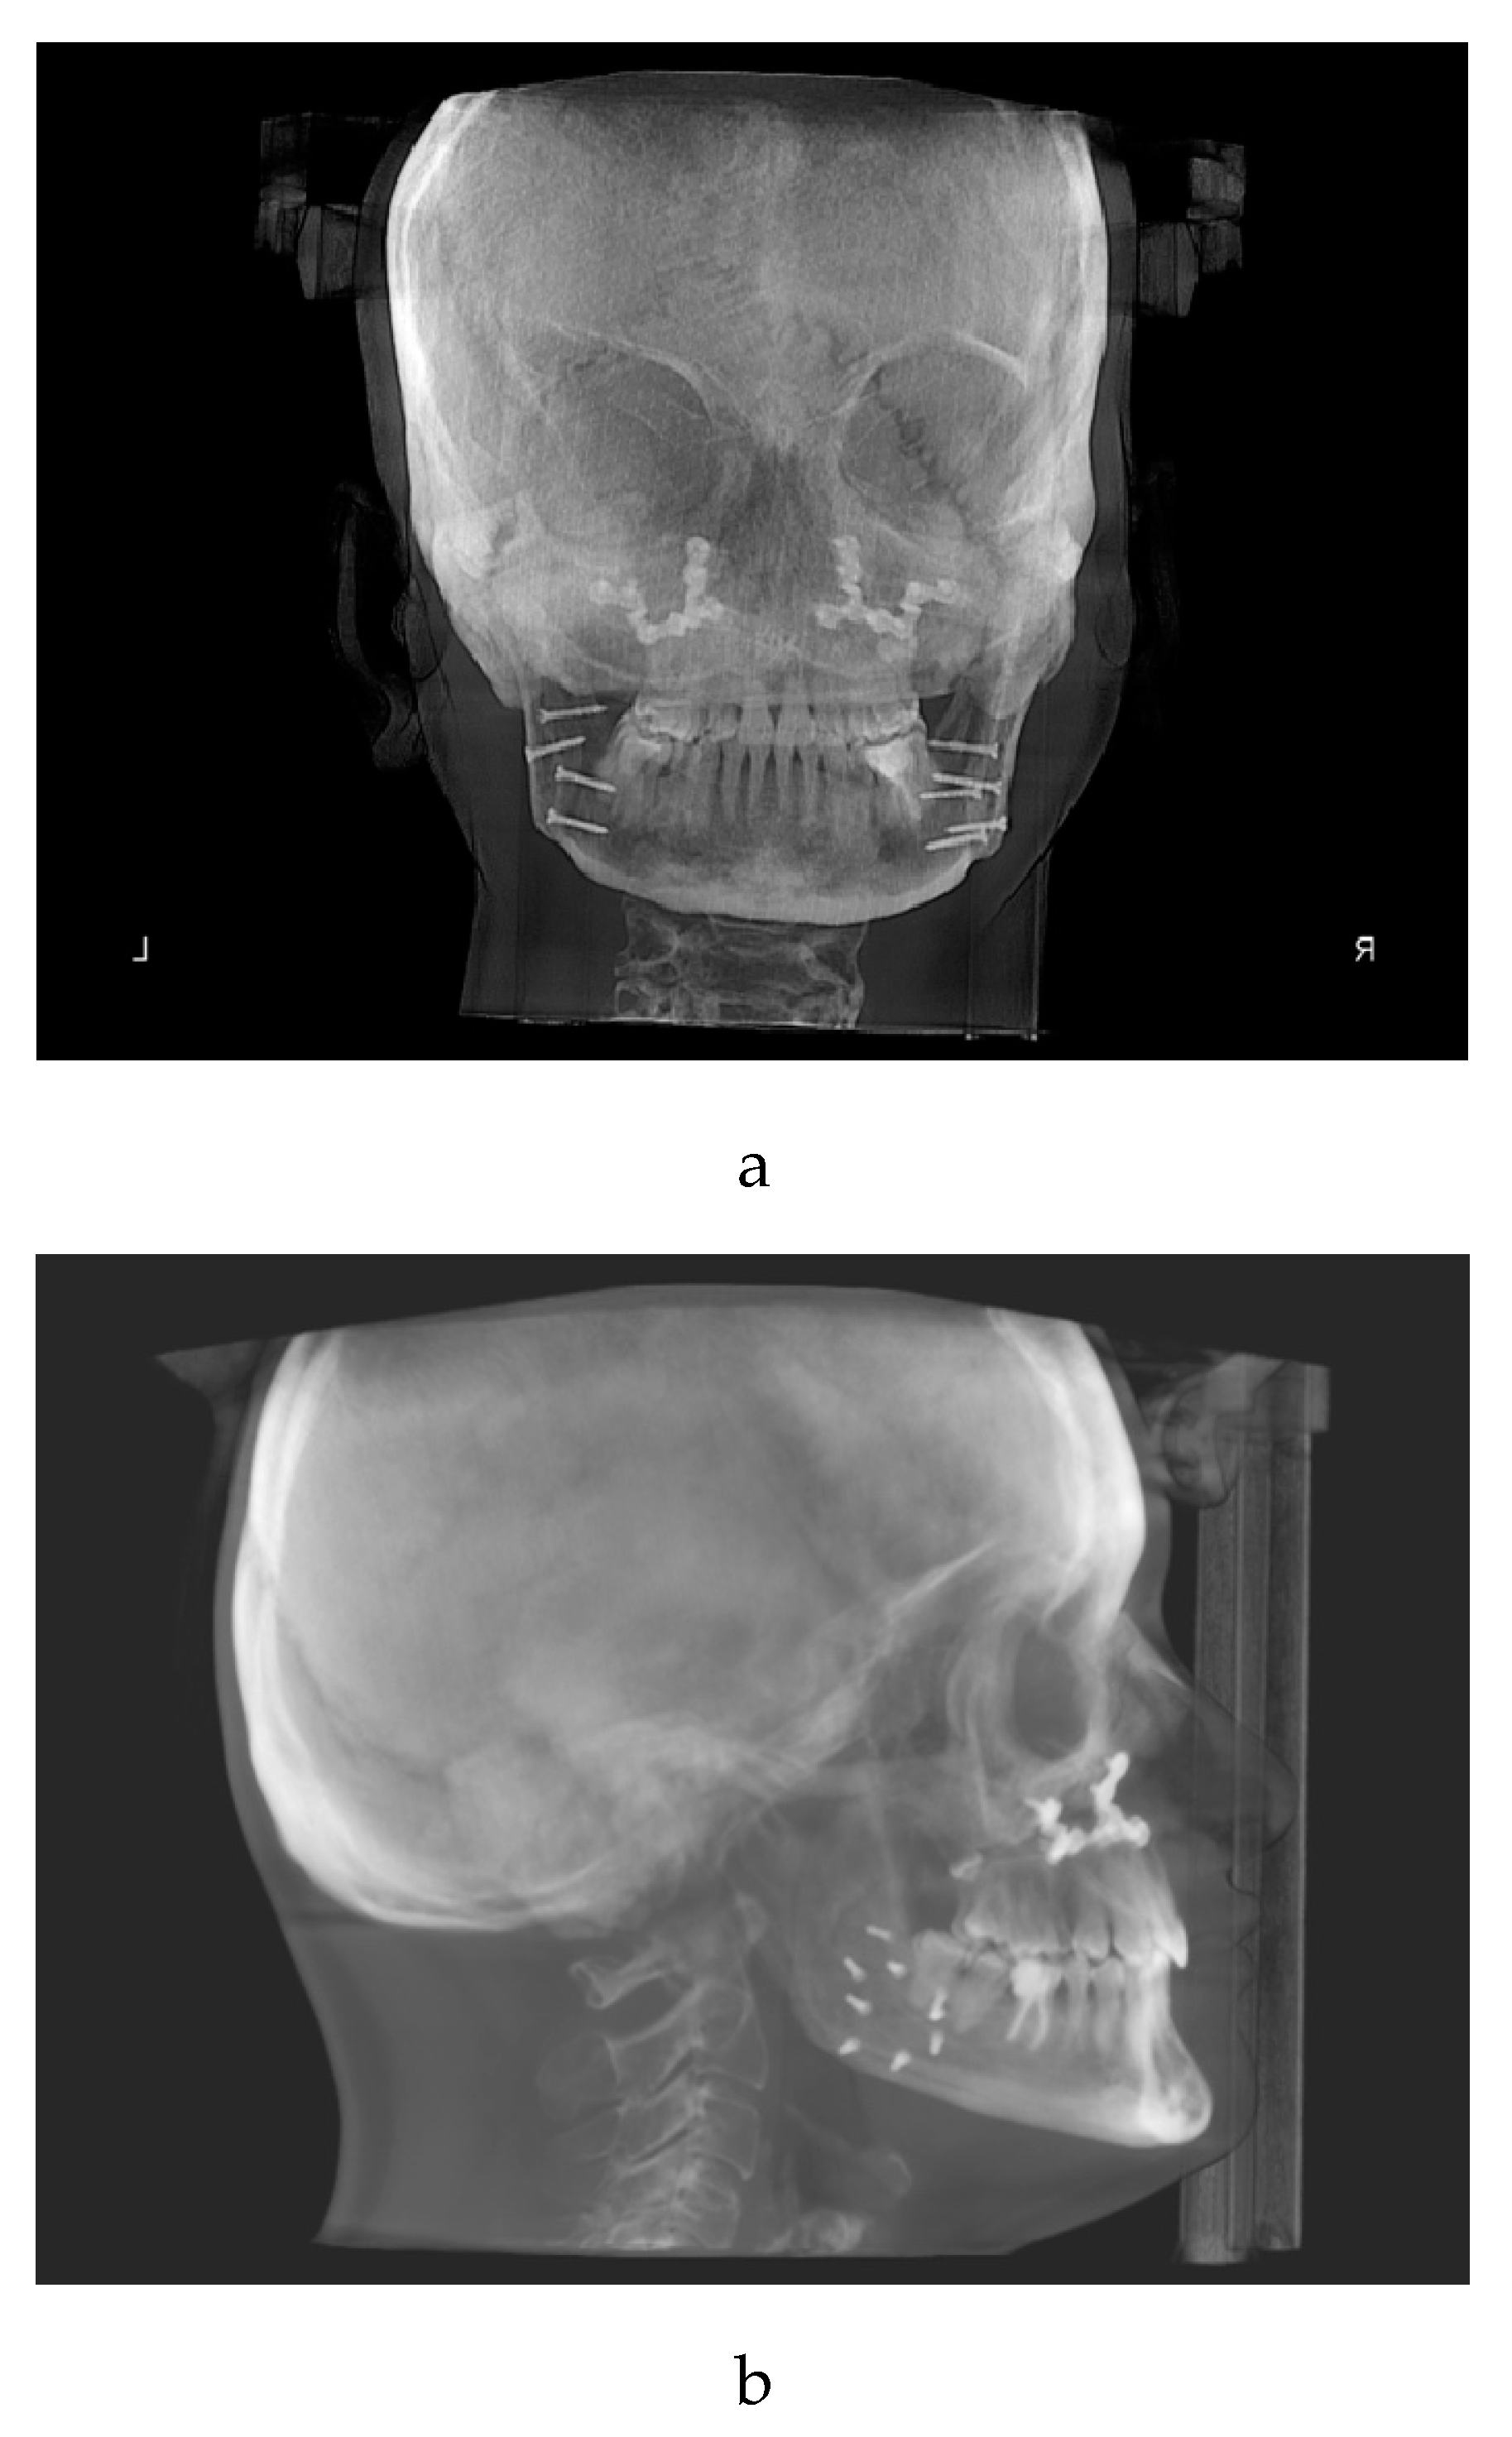

Since May 2021 the patient wore cross arch elastics on elements 1.6, 1.4, 2.6, 2.4, 2.5 to control the high tendency to relapse. (Figure 4)

Figure 4. cross-arch elastics to avoid orthodontic relapse.